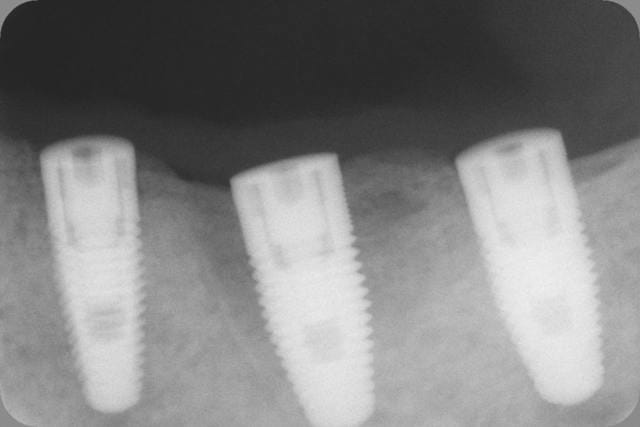

Voici 3 Rx d'un petit cas tout simple : implant Replace Nobel avec pilier titane ID.

Bite-wing fait au contrôle à 1 an. Pour ceux qui douteraient de la compatibilité parfaite :-)